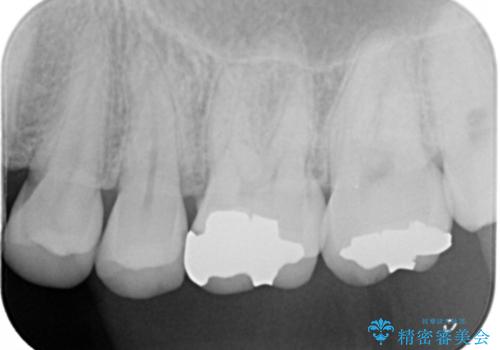

- 左上6番の銀歯をセラミックにしたいと希望され来院された患者様です。

切削量を考慮し、セラミックインレーを選択しました。

銀歯を除去したところ虫歯が深かったので、CRを詰めた上で形態を整えています。